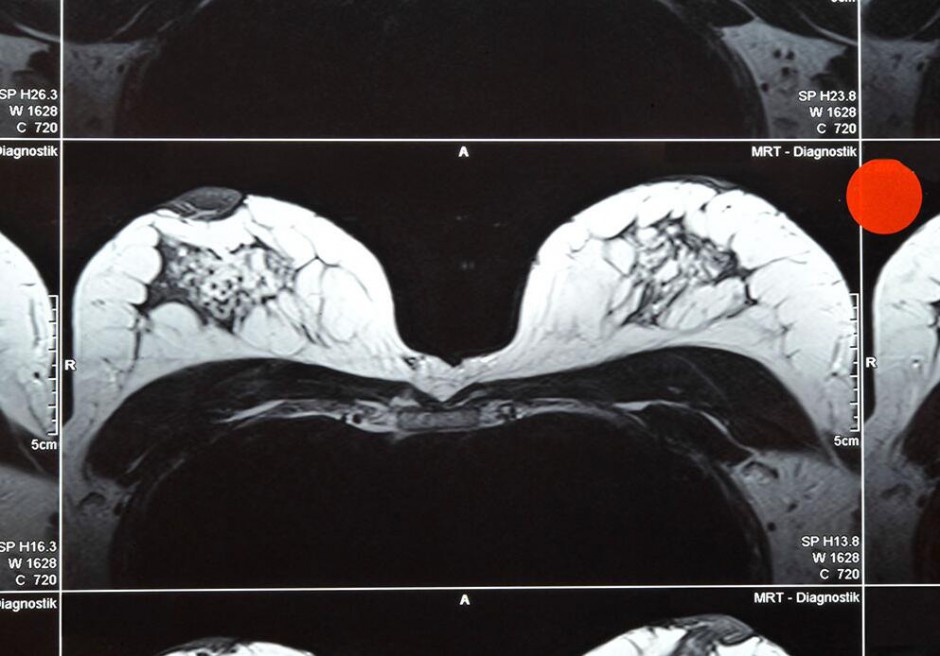

乳腺磁共振的作用

MR由于在乳腺疾病诊断中的高敏感性可以发现乳腺内3mm左右的病灶,而且无电离辐射的优点,在国外已广泛用于乳腺疾病的筛查和诊断。但如何选择适当的乳腺检查时间窗显得至关重要。

女性乳腺的血液循环是随着激素的变化而进行的,其结果造成在乳腺检查中所使用的造影剂随着月经周期中的不同阶段而发生变化,而这种影响在月经的第二周最低,在月经的第一周和第四周最高。所以乳腺的MR检查最佳的时间窗选择是在月经完后的第二周,其次是第三周,而尽量避免在第一周和第四周进行乳腺MR检查。